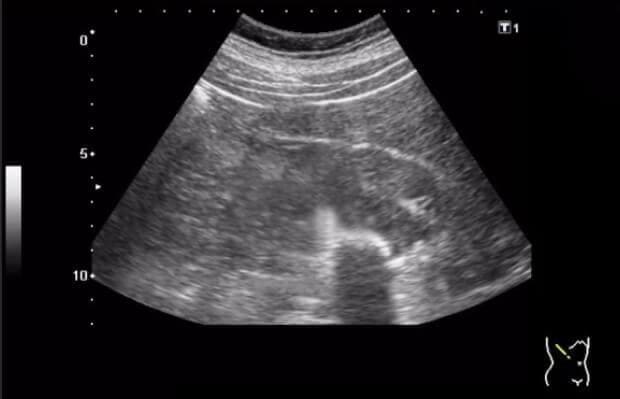

Еден месец подоцна, ултразвукот покажа дека цистата е двојно помала – од 20 mm на 10 mm! A два од трите камења се растворија и ги исфрлив од телото (се сеќавам на болката при мокрење неколку дена пред тоа). Потоа се вратив на редовната доза. Еден месец подоцна, докторот беше шокиран кога направивме ултразвук – бубрезите ми беа чисти!